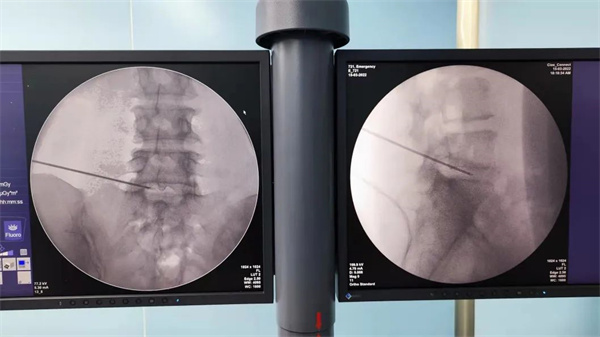

手术如期进行,骨科王辉大夫在C臂引导下熟练地将低温等离子射频刀头置入腰5-骶1椎间盘,进行汽化、消融及成形,手术仅用30分钟便顺利完成,术中未出血,术后仅留有一细小穿刺孔。患者术后即感腰部疼痛消失,活动自如,并于次日出院。

3、拔出针芯,置入腰椎专用等离子刀头,在C臂透视下,仔细确认刀头的位置后,对椎间盘进行消融。